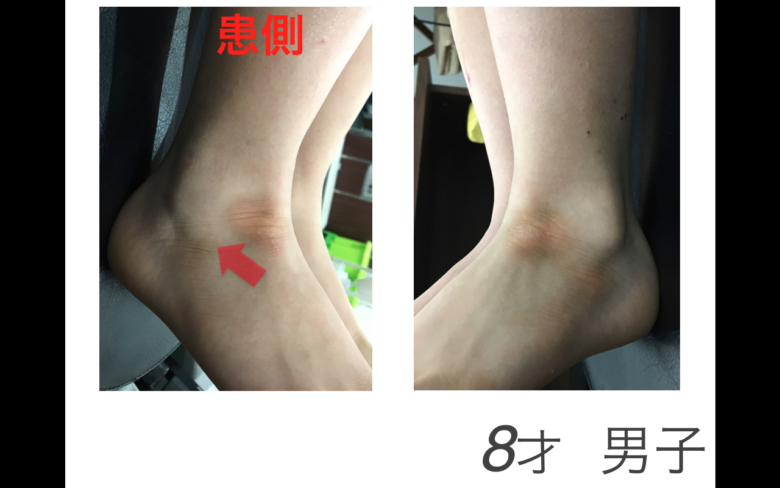

子供さんの足首の骨折

子供さんの足首の骨折

子供さんの足首の骨折

子どもの足首捻挫 長引く腫れや痛み はく離骨折疑って 朝日新聞デジタル